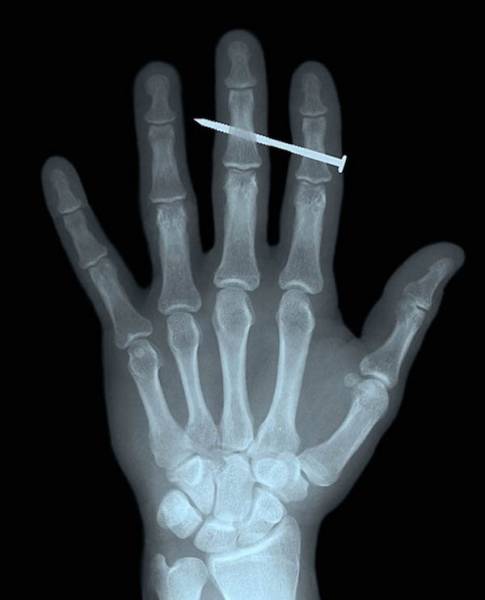

A crew in the finger.